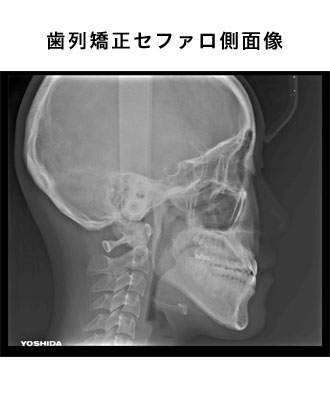

デジタルレントゲン

当院ではあえてCTを採用せず、デジタルパノラマ・セファロレントゲンを採用しました。

CTの1回あたりの撮影の際の被爆量は250μSであるのに対し、デジタルパノラマ・セファロレントゲンは10分の1の25μSvであるからです。

(デジタルパノラマ・デンタルレントゲンは10μS)

被爆量の低減について、医療側の努力が必要であるからです。

3次元的なレントゲンの検査方法として、下記の様な物があります。

方向の異なる画像を読影して診断する事が可能です。